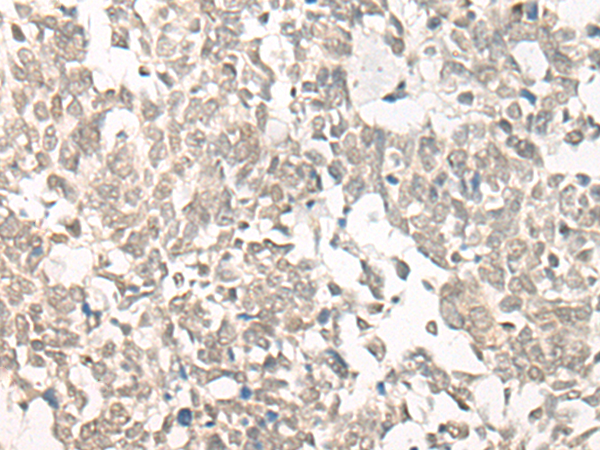

The image is immunohistochemistry of paraffin-embedded Human ovarian cancer tissue using 46985(CPSF3L Antibody) at dilution 1/25. (Original magnification: ?00)

The image is immunohistochemistry of paraffin-embedded Human lung cancer tissue using 46985(CPSF3L Antibody) at dilution 1/25. (Original magnification: ?00)